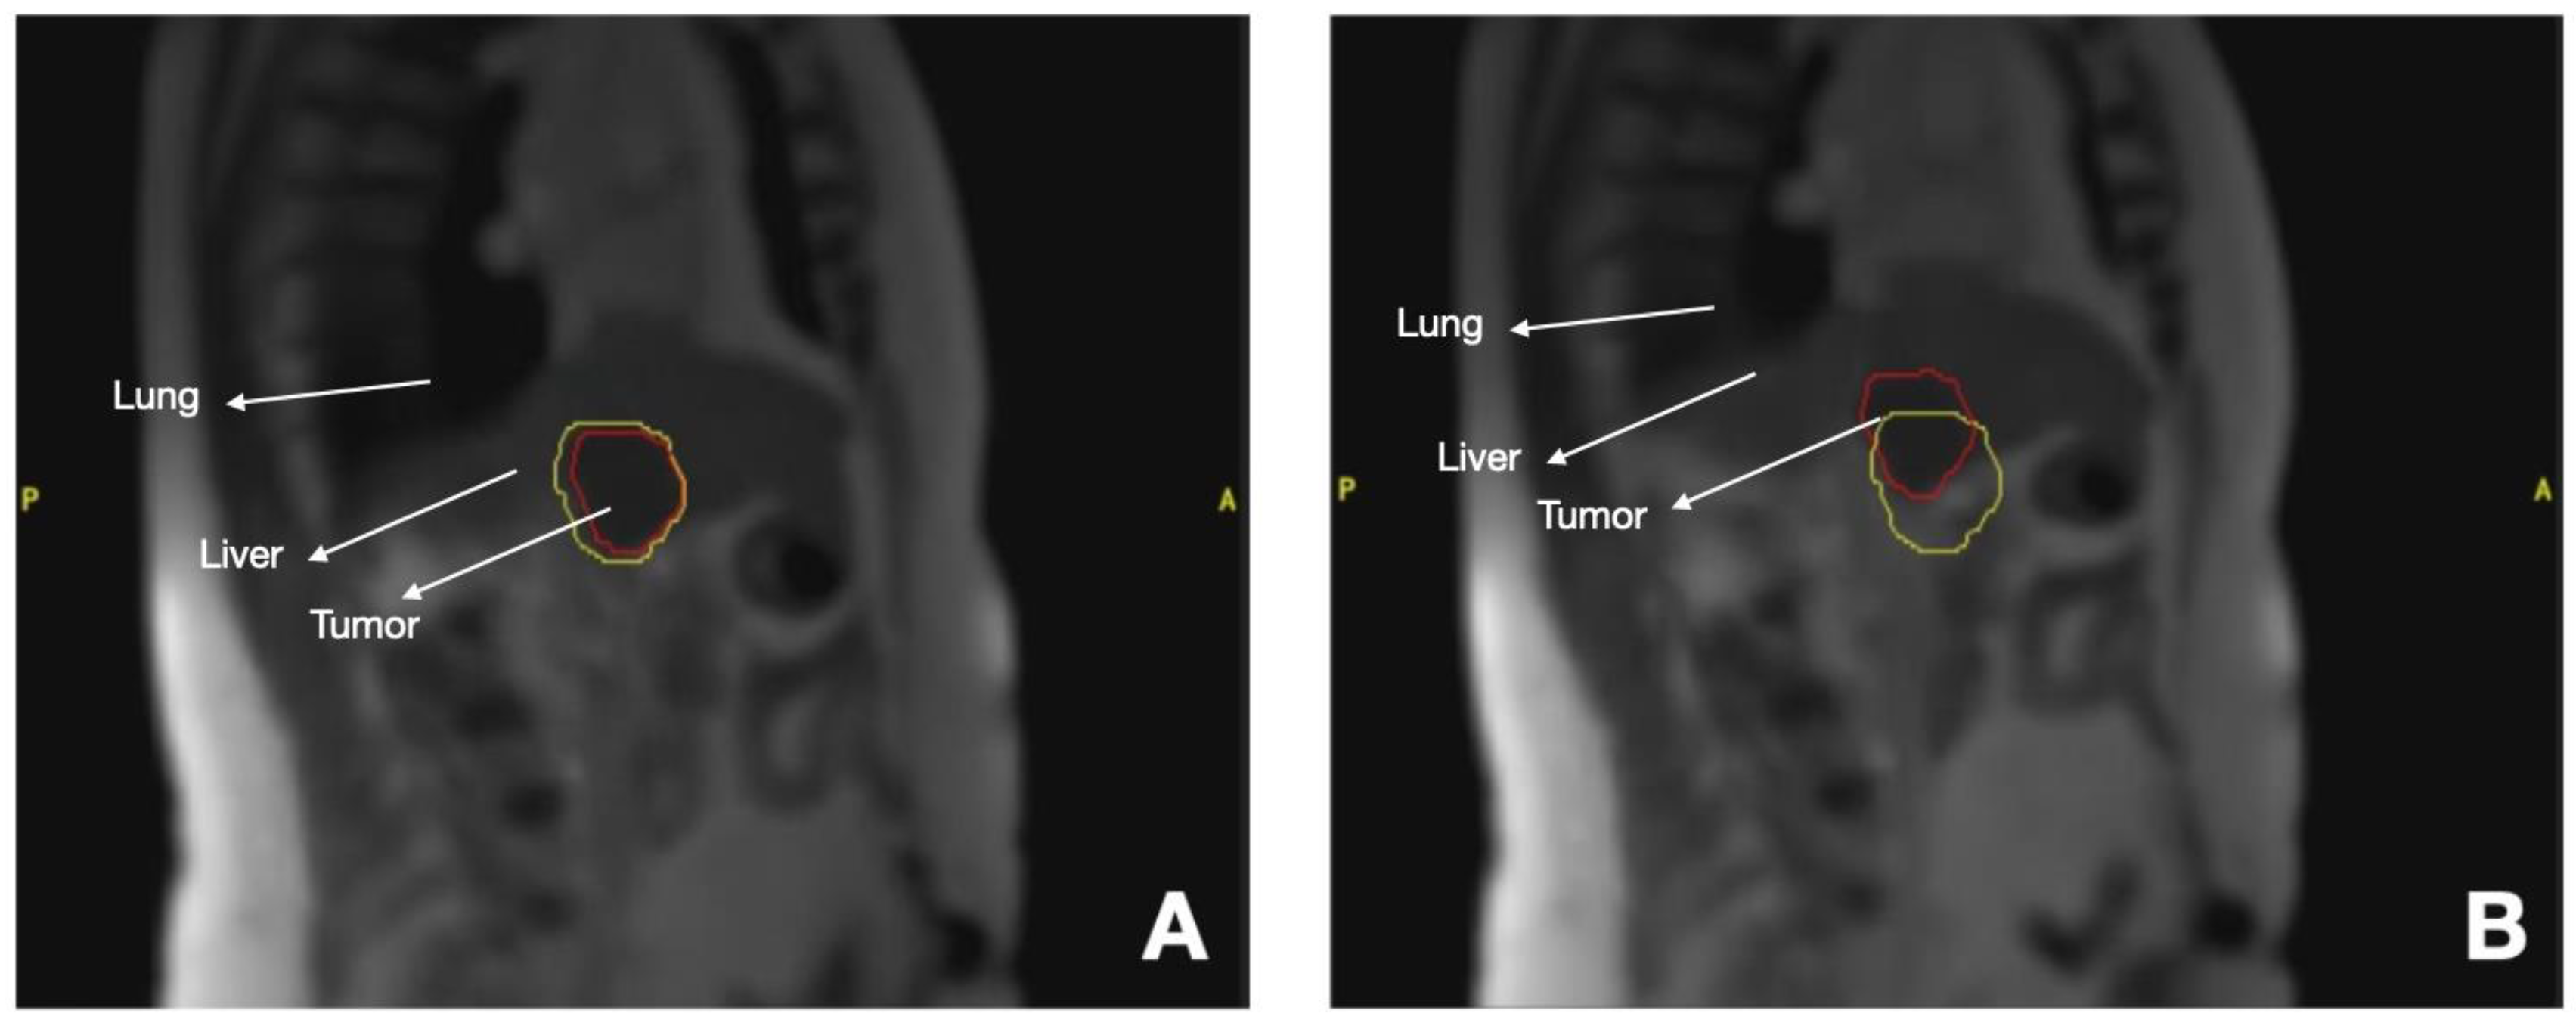

3.3.1. Liver Tumors

- Witt, J.S.; Rosenberg, S.A.; Bassetti, M.F. MRI-guided adaptive radiotherapy for liver tumours: Visualising the future. Lancet Oncol. 2020, 21, e74–e82. [Google Scholar] [CrossRef]

- Hoegen, P.; Zhang, K.S.; Tonndorf-Martini, E.; Weykamp, F.; Regnery, S.; Naumann, P.; Lang, K.; Ristau, J.; Körber, S.A.; Dreher, C.; et al. MR-guided adaptive versus ITV-based stereotactic body radiotherapy for hepatic metastases (MAESTRO): A randomized controlled phase II trial. Radiat. Oncol. 2022, 17, 59. [Google Scholar] [CrossRef] [PubMed]